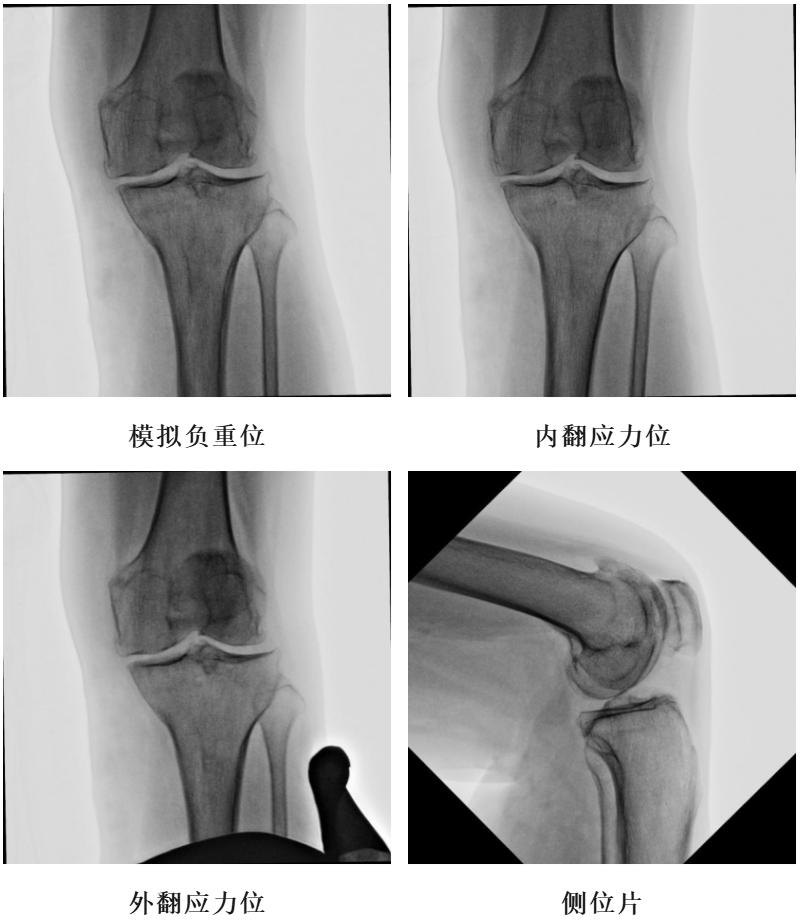

体格检查:左膝内翻畸形,约5°,无屈曲畸形。屈曲20°外翻应力下内翻畸形可纠正,屈曲90°可自行纠正。内侧关节间隙处压痛阳性。活动度:0°~115°。

X-Ray:左膝内侧间隙明显狭窄,站立位内侧间隙消失,外侧间隙正常,膝关节稳定。

术前透视片